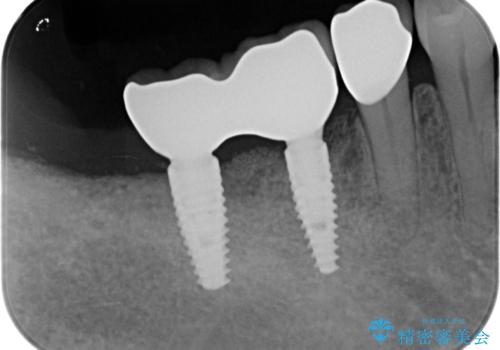

歯周病や虫歯・強度の問題がありながらも無理やり残していた長期的な予後の見込めない歯を抜去し、インプラントを用いてしっかりと噛めるような口腔内環境の確立を目指します。

- 176万円(インプラント×4・チタンカスタムアバットメント×4・ジルコニアクラウン×4・仮歯×4)費用は治療当時の料金となります

見た目が白くなり喜んでいただけただけでなく、しっかりとした噛めるようになり食事を不安なく楽しんでいただけるようになりました。